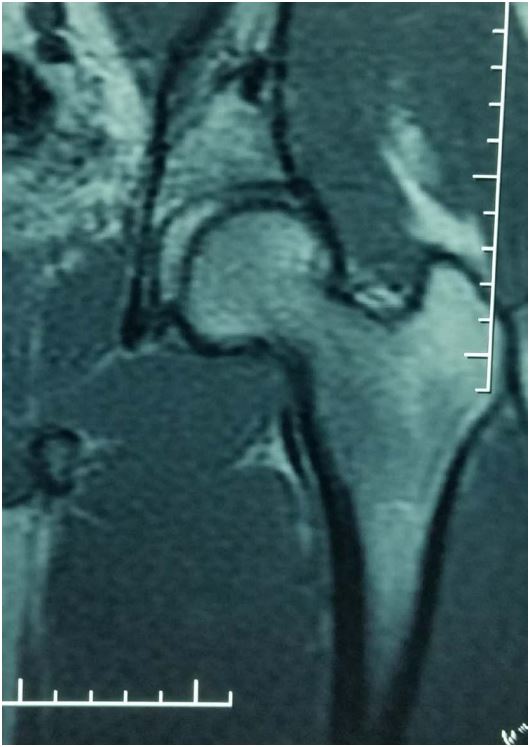

Case 4: Mr. DS was 31 with no medical history, when he was referred to us the 06/09/2013; for a left hip injury follow- ing a road traffic accident. On September 6th 2013, the patient was riding a motorbike when he collided with another motorbike rider, hitting the left knee. On admission, clinical examination revealed abduction, external rotation and flexion at the hip to the same limb. Plain X-rays showed obturator dislocation of the hip (Figure 7). Treatment consisted of closed reduction the next day, followed by 15 days of bed traction. A control MRI 20 months post-traumatic showed no signs of avascular necrosis of the femoral head (Figure 8).

Figure 8: MRI showing no signs of avascular necrosis of the femoral head (patient 4).